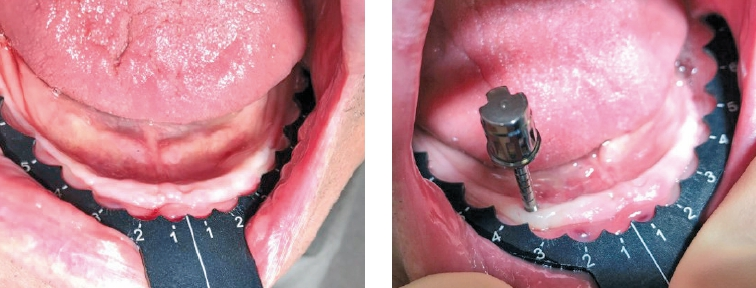

Man bereitet z.B. mit den bereits seit 2006 zugelassenen, einteiligen Champions Kugelkopf-Implantaten (Länge 8 – 10 – 12 – 14 – 16 mm und Durchmessern 2,5 – 3,0 oder 4,0 mm) immer die komplette Arbeitslänge in mm und addiere i.d.R. sogar 4 mm dazu: Für meine Standardlänge 10 mm bereite ich also mit gelbem und weißem Dreikantbohrer transgingival 14 mm auf, um problemlos und ausreichend tief die Implantate inserieren zu können (Abb. 4-9)!

Entscheidend ist bei CNIP, dass man alte OP-Protokolle der Kavitätenaufbereitung hinter sich lässt: So beginnen wir immer mit konischen Dreikantbohrern, welche in der Kompakta maximal mit 250 U/Min. und in der Spongiosa folgend mit 50-70 U/Min. betrieben werden! Fährt man diese niedrigen Geschwindigkeiten, so verbleibt der Dreikantbohrer immer in der Spongiosa und wird durch die bukkale und orale Kompakta quasi „navigiert“. Auf diese Weise kann der „gelbe“ Bohrer keine kompakte Knochenwand perforieren. Zudem kontrollieren wir die Kavität-Bohrungen immer mit einer dünnen, flexiblen und ausreichend langen Knochensonde: ‚KKK‘ = Knochen-Kavitäten-Kontrolle.